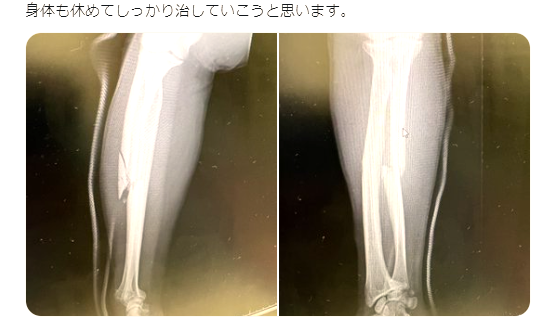

昇侍公開のレントゲン写真。左写真は骨に亀裂が入っているのが分かる(昇侍Twitterより)